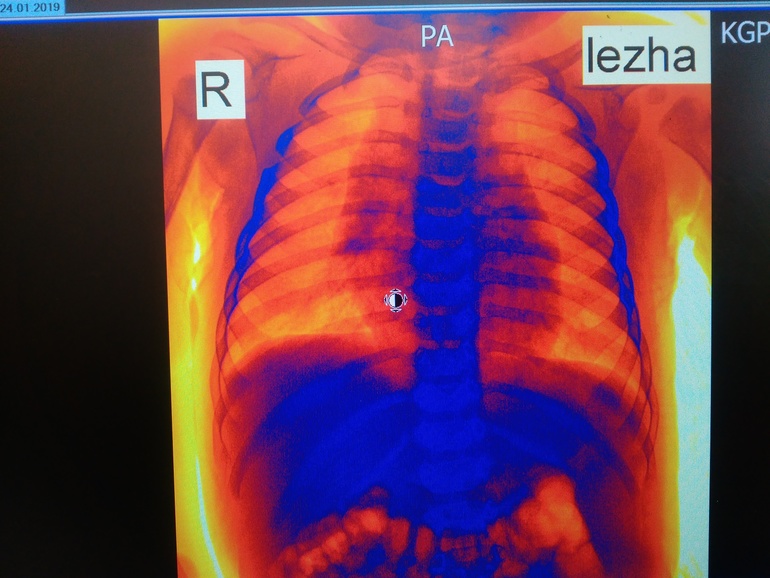

ОртопедияВсем здравствуйте! Сегодня ходили на рентген с сыночком на 6 месяцев,нас отправил хирург - выпирали нижние ребрышки. В итоге: сращение 4-5 ребра справа(никто такого поворота событий не ожидал,обнаружилось случайно),хондроматоз 6-7 ребра слева,кардиопатия. Завтра иду брать направление к хирургу-ортопеду в областной центр,но там скорее всего очередь. Хотела спросить девочки может кто-то с таким сталкивался? Может ошибка? Прикрепляются снимки (рентгенолог сам сказал сфотографируй потом покажешь врачу).Успокойте меня плииииззззз..